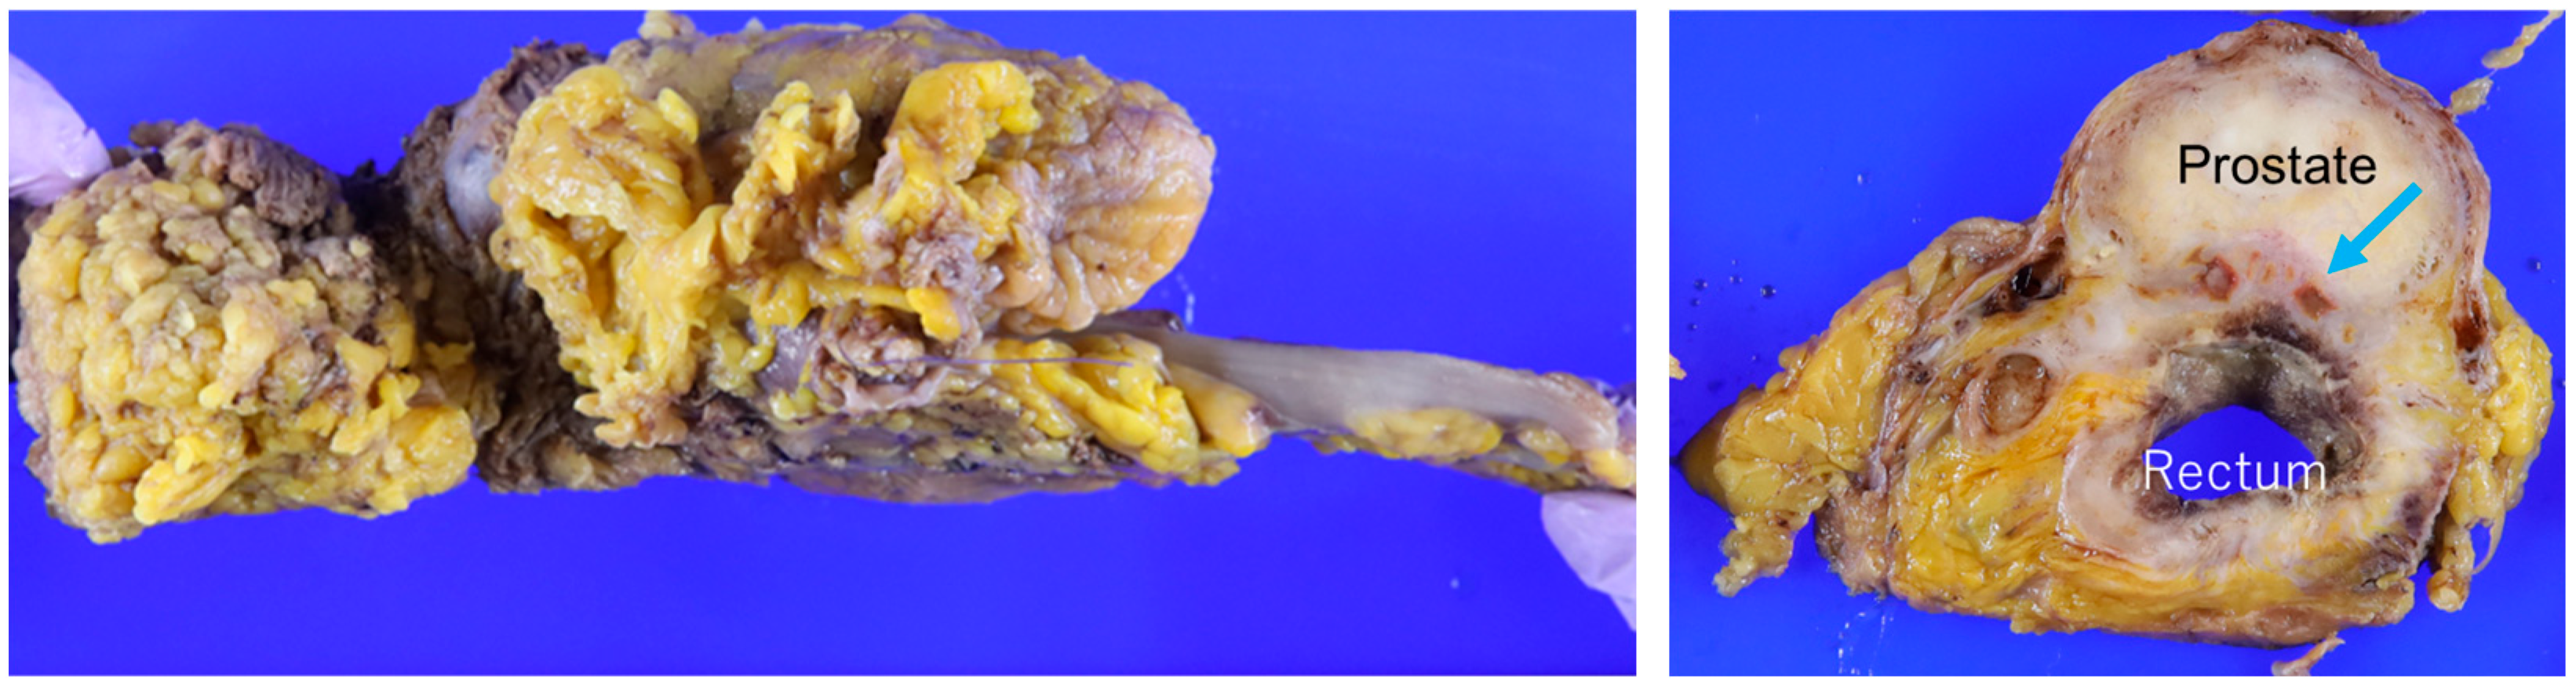

3. Results